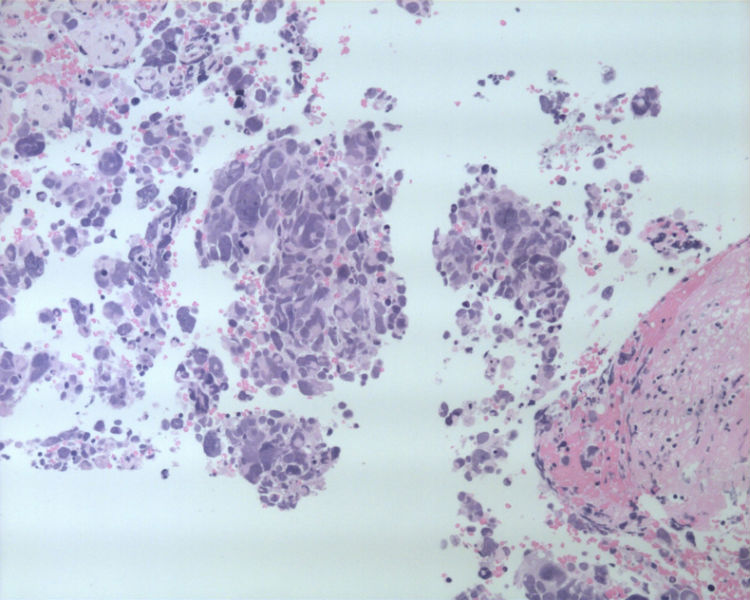

男性,50岁,右锁骨上淋巴结穿刺。

• 男性,50岁,右锁骨上淋巴结穿刺。图1

这是一例我以前穿刺的病例。当时涂片发现淋巴细胞的背景中散在大而非常异形的细胞。细胞没有成巢现象。

其余的视野几乎和这些差不多。

基本都是淋巴细胞背景中散在异形非常明显的细胞。细胞无成巢现象。